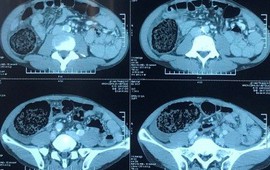

Tiến hành siêu âm, kiểm tra ổ bụng, các bác sĩ phát hiện bệnh nhân bị đầy hơi và chảy nhiều máu trong ổ bụng nên được chỉ định phẫu thuật cấp cứu.

Trong khi tiến hành phẫu thuật, các bác sĩ phát hiện bệnh nhân bị vỡ đại tràng và rách 17 chỗ khác dọc theo đại trực tràng. Do đó, ê kíp phẫu thuật phải khâu vết thủng đại tràng cũng như các vết rách rải rác và rửa ổ bụng, sau đó đặt dẫn lưu cho bệnh nhân.

Đến ngày 20/8, tình trạng sức khỏe của bệnh nhân bị vỡ đại tràng góc gan do bơm hơi vào hậu môn đã ổn định sức khoẻ, hết đau, chướng bụng và có thể xuất viện trong tuần tới.